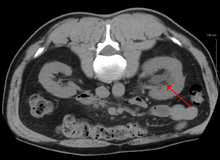

Imaging studies, such as an intravenous urogram (IVU), ultrasound, CT or MRI, are also important investigations in determining the presence and/ or cause of hydronephrosis. Whilst ultrasound allows for visualisation of the ureters and kidneys (and determine the presence of hydronephrosis and / or hydroureter), an IVU is useful for assessing the anatomical location of the obstruction. Antegrade or retrograde pyelography will show similar findings to an IVU but offer a therapeutic option as well. Real-time ultrasounds and color-flow Doppler tests in association with vascular resistance testing helps determine how a given obstruction is effecting urinary functionality in hydronephrotic patients.[12]

The choice of imaging depends on the clinical presentation (history, symptoms and examination findings). In the case of renal colic (one sided loin pain usually accompanied by a trace of blood in the urine) the initial investigation is usually a spiral or helical CT scan. This has the advantage of showing whether there is any obstruction of flow of urine causing hydronephrosis as well as demonstrating the function of the other kidney. Many stones are not visible on plain X-ray or IVU but 99% of stones are visible on CT and therefore CT is becoming a common choice of initial investigation. CT is not used however, when there is a reason to avoid radiation exposure, e.g. in pregnancy.